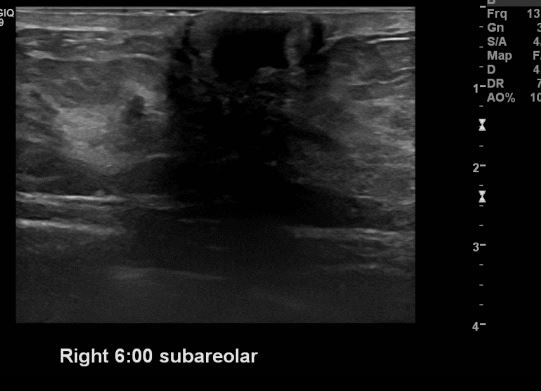

건강검진상 이상 소견으로 내원하여 경과 관찰하시는 40대 여성분으로

유방 정기초음파상 우측 유방 6시 방향 유두 밑 의심스러운 부분 조직검사 시행하여

우측 유관암 진단 되었습니다.